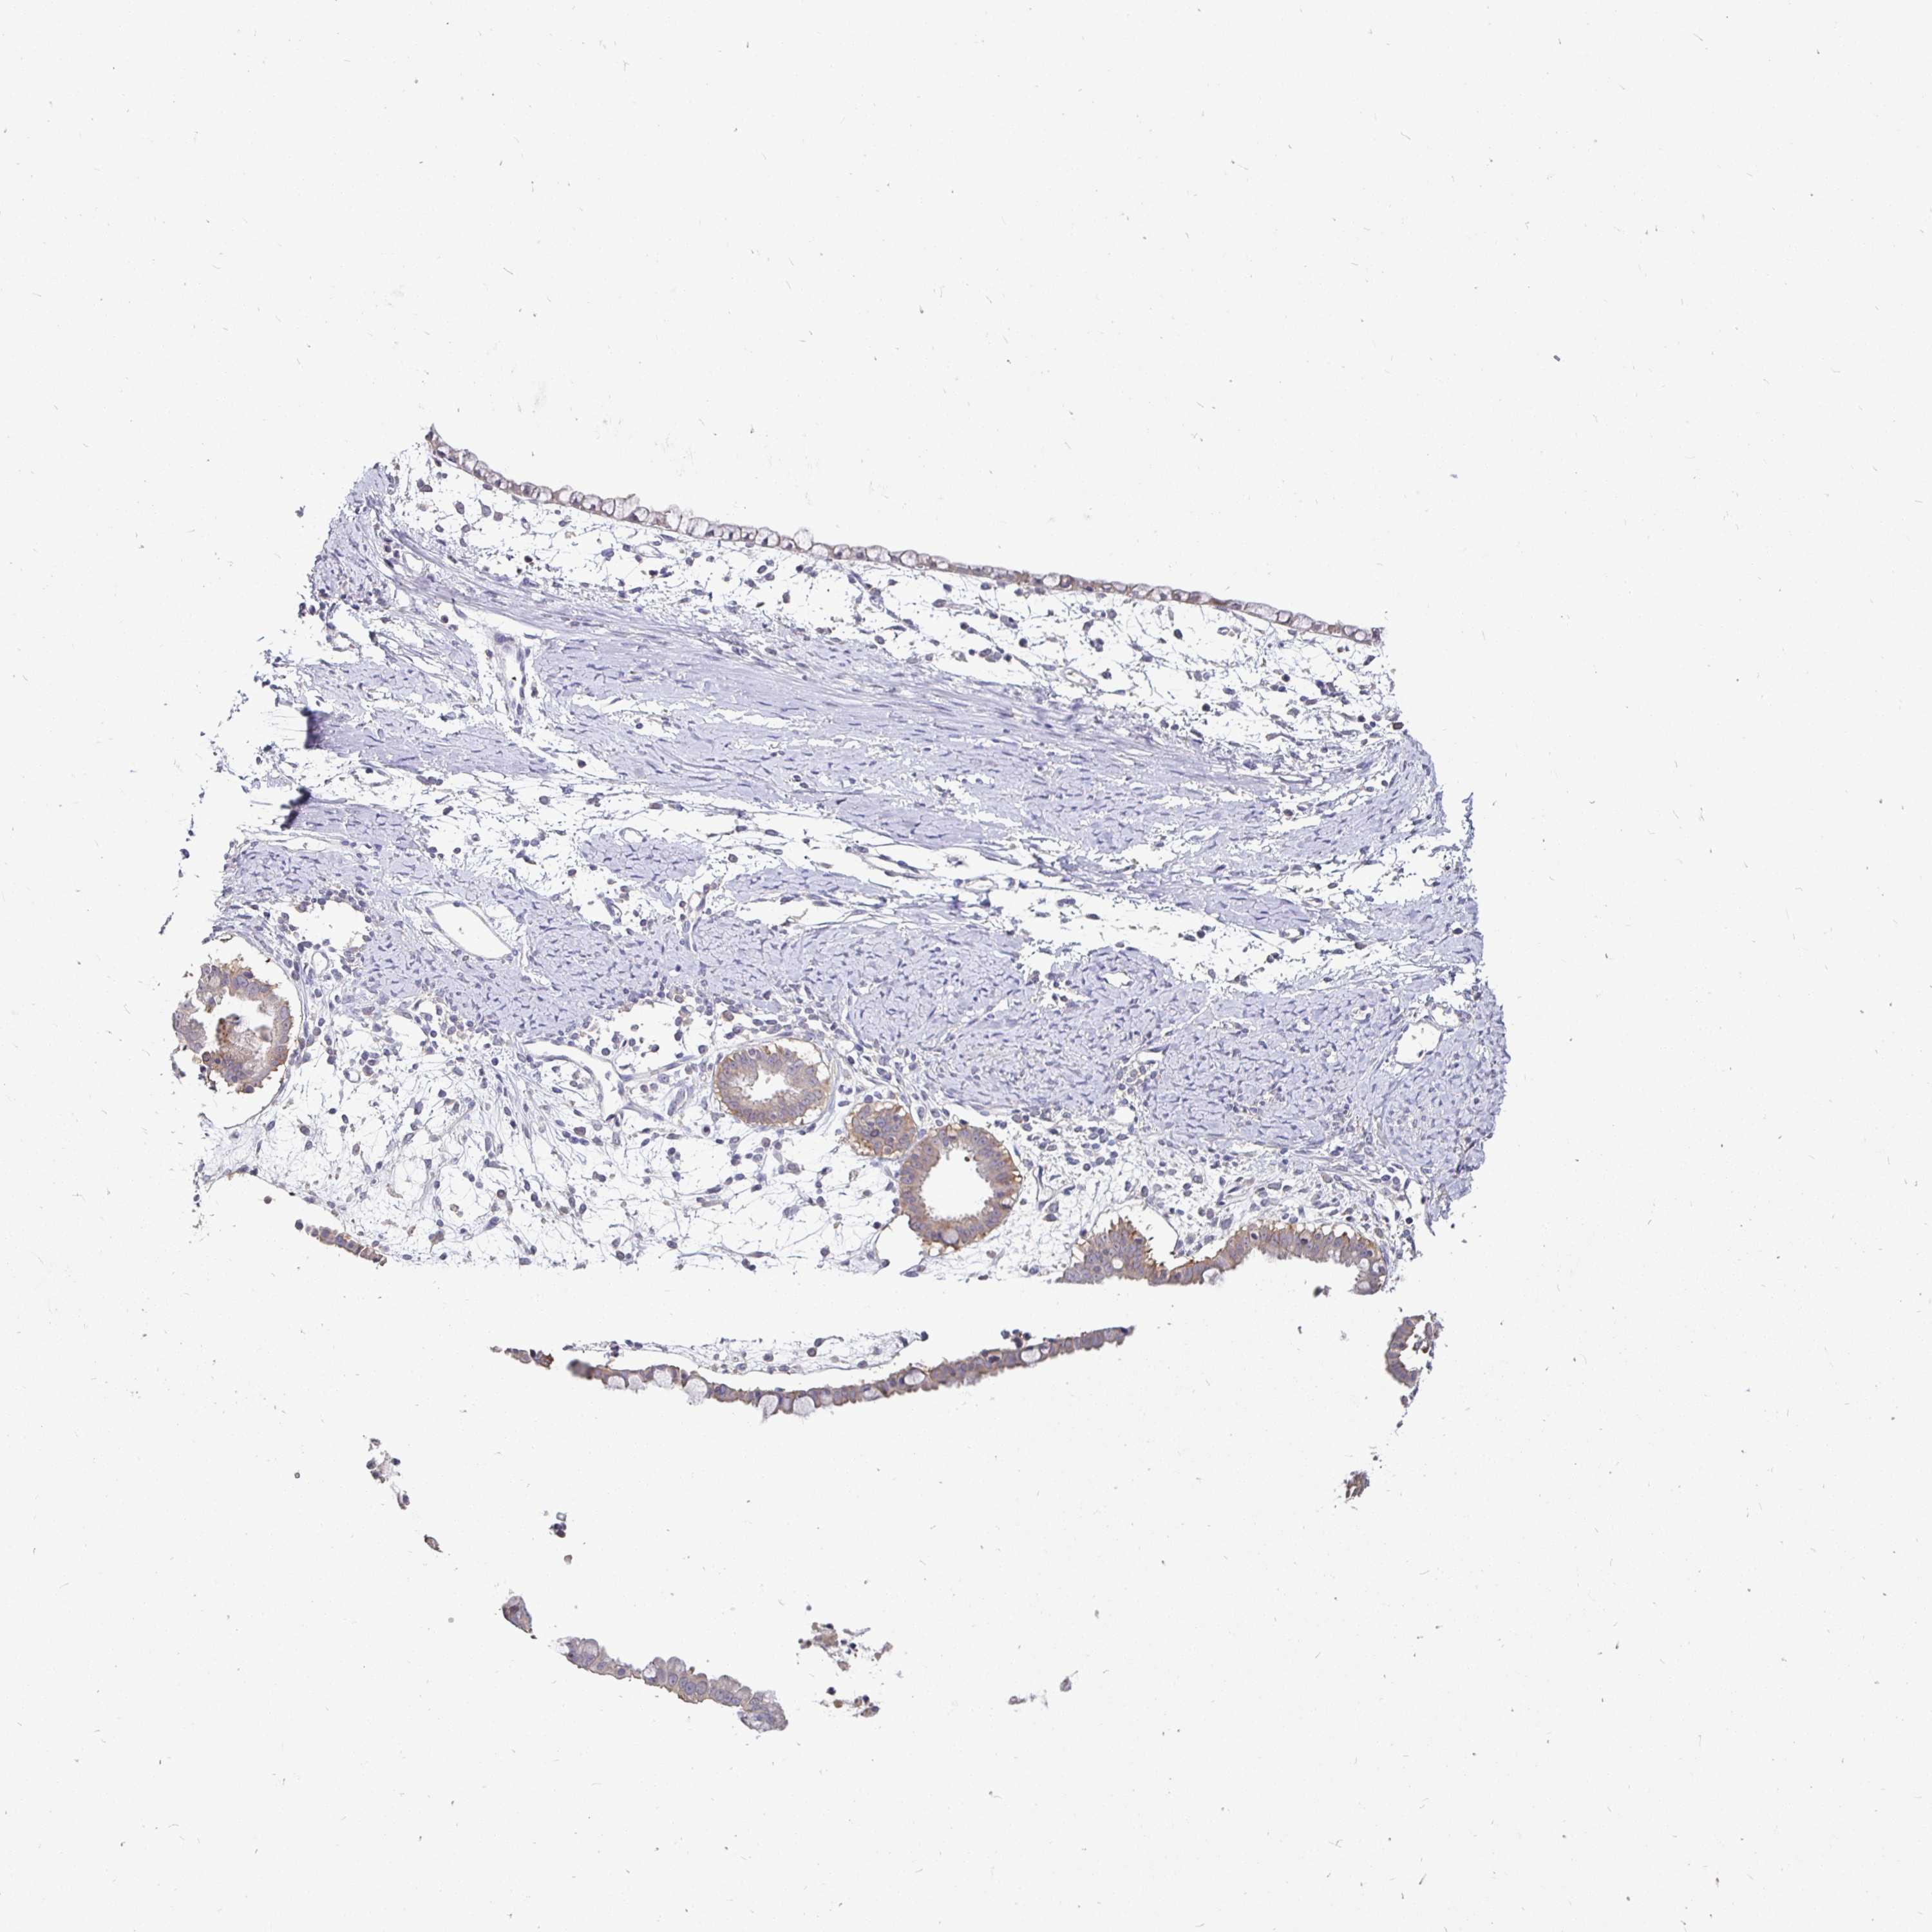

OVARIAN CANCER - Protein expressioni

A mouse-over function shows sample information and annotation data. Click on an image to view it in a full screen mode. Samples can be filtered based on level of antibody staining by selecting one or several of the following categories: high, medium, low and not detected. The assay and annotation is described here.

Note that samples used for immunohistochemistry by the Human Protein Atlas do not correspond to samples in the TCGA dataset.

Antibody stainingi

Antibody staining in the annotated cell types in the current human tissue is reported as not detected, low, medium, or high, based on conventional immunohistochemistry profiling in selected tissues. This score is based on the combination of the staining intensity and fraction of stained cells.

Each image is clickable and will lead to virtual microscopy that enables deeper exploration of all samples and also displays staining intensity scores, fraction scores and subcellular localization as well as patient and tissue information for each sample.

Antibody HPA058432

Antibody CAB022079

Cystadenocarcinoma, serous, NOS

Cystadenocarcinoma, mucinous, NOS

Adenocarcinoma, NOS

Carcinoma, endometroid

Carcinoma, NOS